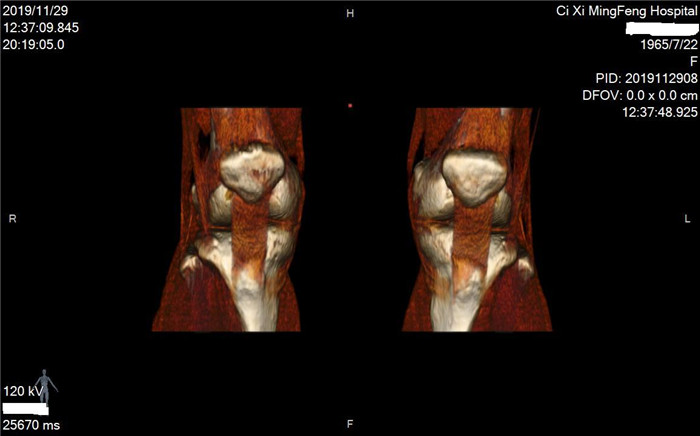

明峰CT搭載了領(lǐng)先的硬件技術(shù)平臺及系統(tǒng),強大的掃描能力可滿足臨床的各種要求,呈現(xiàn)更極致的細節(jié),為各臨床科室提供高品質(zhì)的圖像。薄層掃描,消除部分容積效應,提高各向同性。配合高分辨率算法,有助于細微結(jié)構(gòu)和形態(tài)學顯示。